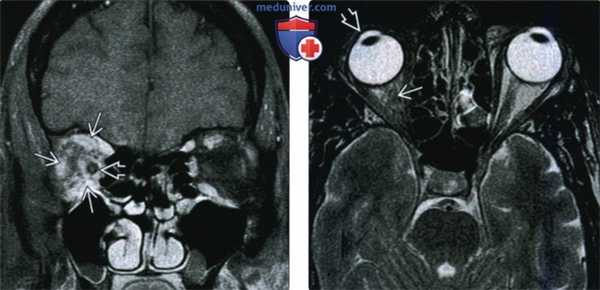

(Слева) У пациента с болезненным неподвижным правым глазом при МРТ Т1ВИ FS с КУ в корональной проекции внутри и вне мышечного конуса определяется обширная зона контрастирования с нечеткими контурами. Глазодвигательные мышцы увеличены в размерах, их контуры также нечеткие. Обратите внимание на инфильтрацию вокруг влагалища зрительного нерва.

(Справа) При аксиальной МРТ Т2 ВИ у этого же пациента в правой глазнице определяется гипоинтенсивная зона инфильтрации с нечеткими контурами. Слабый Т2-сигнал указывает на хронический фиброз, вызванный склерозирующим идиопатическим воспалением глазницы (псевдотумором). Обратите внимание: неподвижный глаз отклонен кнаружи.

(Слева) У пациента с ограничением подвижности глазного яблока при MPT Т1 ВИ FS с КУ в коро-нальной проекции в левой глазнице внутри и вне мышечного конуса визуализируется плохо контрастируемая инфильтративная ткань, отмечается небольшое увеличение размеров глазодвигательных мышц. В этом случае комплексная терапия оказалась эффективной.

(Справа) У пациента с болями в области лица и офтальмоплегией при МРТ Т1BИ FS с КУ в корональной проекции определяется выбухание твердой мозговой оболочки латеральной стенки и контрастирование правого кавернозного синуса по сравнению с контрлатеральным кавернозным синусом. Обратите внимание на уменьшение калибра кавернозного сегмента внутренней сонной артерии. Синдром Tolosa-Hunt.